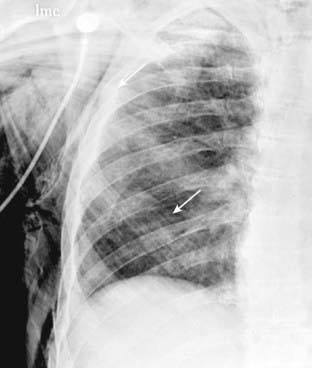

Figure 8-5 Bullous disease, right upper lobe.

A thin, white line is visible on this close-up of the right upper lobe (solid white arrows) and no lung markings are seen peripheral to it. Unlike the visceral pleural line of a pneumothorax, this white line is convex away from the chest wall and does not parallel the curve of the chest wall. This is the classical appearance of a bulla in a patient with emphysema. It is important to differentiate between a pneumothorax and a bulla because inadvertently placing a chest tube into a bulla will almost always produce a pneumothorax which may be difficult to re-expand. The walls of several bullae are visible in this patient (dotted white arrows). On rare occasions, the bullae can grow so large as to render the hemithorax seemingly devoid of visible lung tissue (vanishing lung syndrome).

Figure 8-6 Bullous disease on right; pneumothorax on left.

This axial section from a chest CT demonstrates the different appearances of bullous disease, seen on the right with its border convex away from the chest wall (dotted white arrow), and a pneumothorax seen here on the left with its border convex toward and paralleling the chest wall (solid white arrow). This patient also has subcutaneous emphysema on the left (solid black arrow).